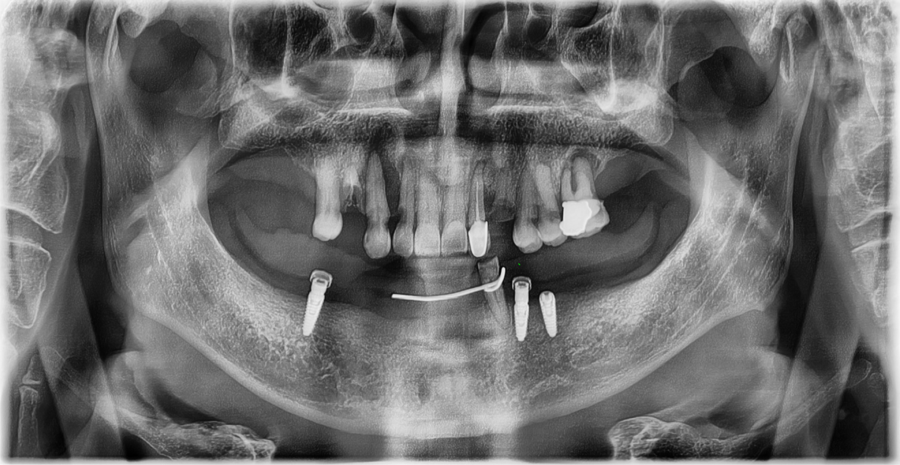

정밀 진단

저희 잠실 치과 서울오브치과병원에서는

시니어 환자분들도

3D 스캐너·구강내시경·교합 검사를 통해

현재 치아 상태를 세밀하게 확인하고 있습니다.

검사 결과,

앞니는 치질이 충분히 남아 있어

과도한 삭제 없이도 라미네이트가 가능했고,

잇몸 상태도 안정적으로 유지되고 있었습니다.

교합 또한 큰 문제 없이 맞물리고 있어

기존 보철물의 색과 형태만 개선해도

더 자연스럽고 균형 잡힌 앞니 라인으로

회복될 수 있는 케이스였습니다.